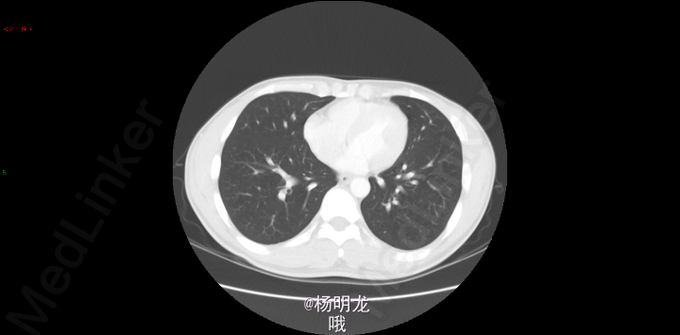

2014.9因大便带血,行肠镜检查,病理提示直肠癌。 2014-10-8胸部CT:双肺新出现多发微小结节,大者约0.2cm,高度警惕肺内转移。 遂于我院行FOLFIRI方案化疗,10周期。